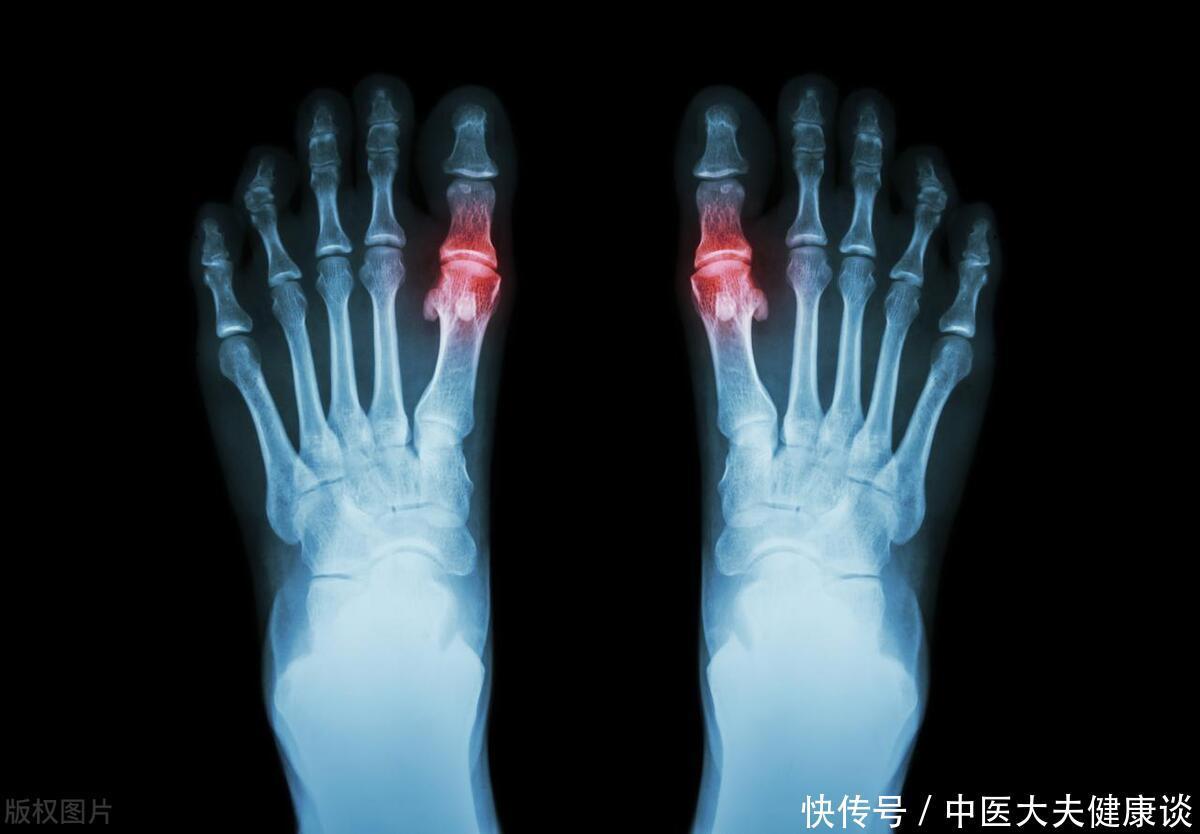

《营养前沿》揭晓:豇豆膳食纤维成效斐然,助力降低血清尿酸,痛风隐忧得以缓解。这主要得益于膳食纤维对肠道功能的改善和对尿酸代谢的促进作用。值得注意的是,豇豆虽然含有一定的嘌呤,但其含量相对较低(每100克约含30毫克嘌呤),远不及海鲜、动物内脏等高嘌呤食物。因此,对于高尿酸患者来说,适量食用豇豆是安全的,甚至有助于控制尿酸水平。